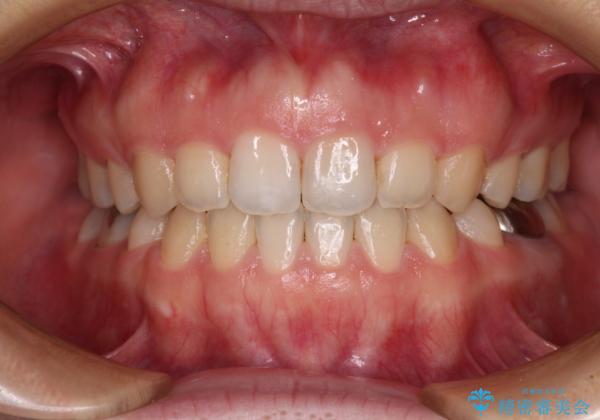

- 口元の膨らみが気になるとのことで来院された患者様です。

非抜歯で口元の突出感を少し改善させる治療も提案しましたが、最大限口元を引っ込めたいとのことでした。

上下左右第一小臼歯4本を抜歯し、ワイヤー装置により矯正治療を行うこととしました。

治療は順調に進み、予定された期間で終了することができました。

装置除去後には、スッキリとした口元となり、大変満足していただきました。